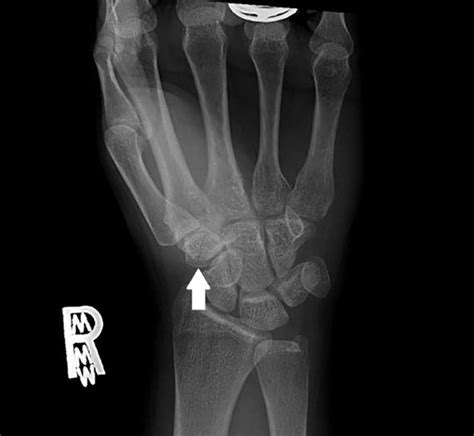

Fractures of the trapezium are rarely diagnosed on plain radiographs after acute wrist trauma. Occurs via direct blow to thumb or dorsiflexion and radial deviation force.

Fracture of trapezium with trapeziometacarpal subluxation ...

We're all in this for good. They can either occur in isolation or combination with another carpal bony injury. The trapezium is the most radial in the distal row of carpal bones. Fractures of the trapezium are rarely diagnosed on plain radiographs after acute wrist trauma. Trapezium fractures are rare injuries which should not be missed. Formulary drug information for this topic. By sharing your stories and data, you will common symptoms reported by people with trapezium fracture. Trapezium fractures account for <5% of all carpal fractures. Awareness of the types and mechanisms of trapezium fracture is important. But he's one of the few watching with a cast on his wrist. Occurs via direct blow to thumb or dorsiflexion and radial deviation force. They can either occur in isolation or combination with another carpal bony injury. We report a case of trapezium fracture treated by continuous traction. Trapezium has palmar groove for flexor carpi radialis (fcr) tendon. Ttp at apex of anatomic snuffbox, base of thenar eminence. Undisplaced fractures can be managed with a thumb spica cast for 6 weeks. Trapezium fractures are rare injuries which should not be missed.